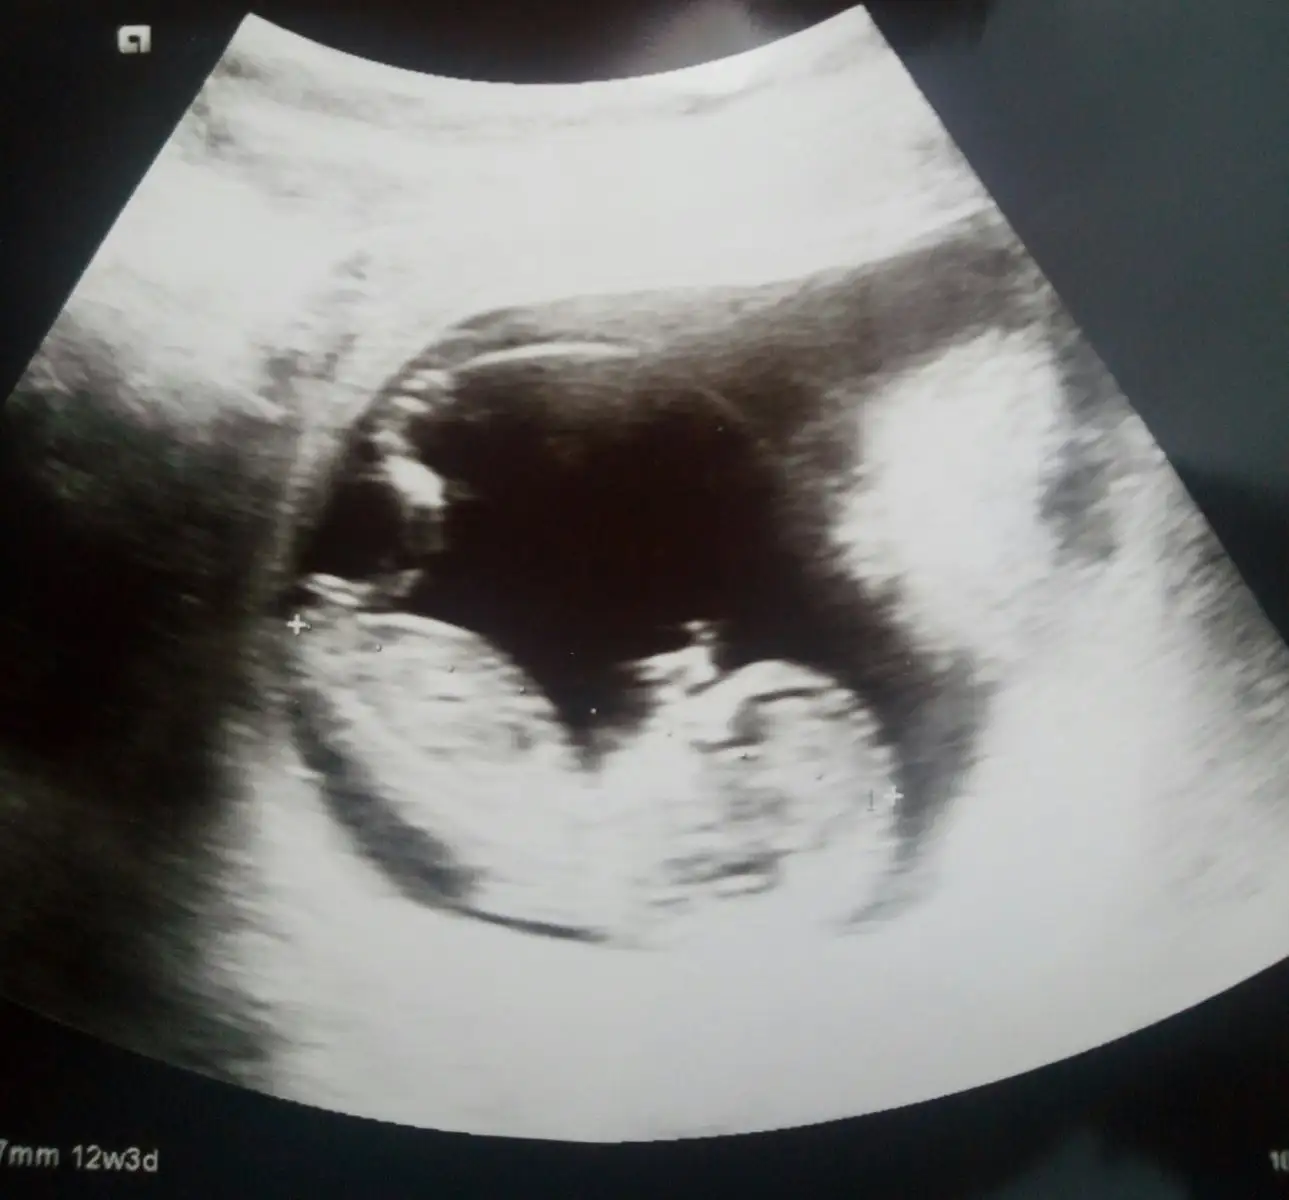

Canım bebeğin kız gibi görünüyor. RABBİM gönlündekini nasip etsinBizimkinide göremedi haftasıyla uyumlu gayet sağlıklı gözüküyo dedi geldik kızlar resimlerini atayım bari siz yorumlayın bebeğimiEki Görüntüle 2227989 Eki Görüntüle 2227990

İnşallah hayırlısıyla erkekdir ikimizinkideCanm senin ultrason gpruntune bilgili bir i attim erkege benzetti insallah. Erkek olur hayirlisiyla

Hayırlısı artık canım bende anlamadım bu sefer ama kafa yapısı kızıma göre yuvarlak bi ondan erkek gibi ama nubu belli değil bi çıkıntı var ama nubmu değişik bişey anlamadım da hayırlısı olsun sağlıklı olsundaCanım bebeğin kız gibi görünüyor. RABBİM gönlündekini nasip etsin

Canım kızında bu haftalardaki ultrasonda başı sağdamıydı ve duruşu böylemiydi. Nasip kısmet RABBİM alnımıza ne yazmışsa hakkımızda hayırlısı odur demekki.Hayırlısı artık canım bende anlamadım bu sefer ama kafa yapısı kızıma göre yuvarlak bi ondan erkek gibi ama nubu belli değil bi çıkıntı var ama nubmu değişik bişey anlamadım da hayırlısı olsun sağlıklı olsunda

Başı sağdaydı kızımın ama duruşunu hatırlamıyorum 3arkadaşımın erkek bebeklerinin kafasıda böyle sağda o olaya pek inanmıyorumCanım kızında bu haftalardaki ultrasonda başı sağdamıydı ve duruşu böylemiydi. Nasip kısmet RABBİM alnımıza ne yazmışsa hakkımızda hayırlısı odur demekki.